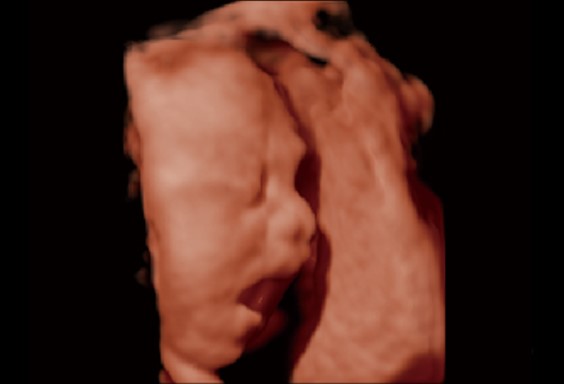

S-Live/Hdlive/5D

S-Live cho phép hiển thị chi tiết các đặc điểm giải phẫu tinh vi, từ đó cho phép chẩn đoán trực quan với hình ảnh 3D thời gian thực và giao tiếp với bệnh nhân phong phú hơn.